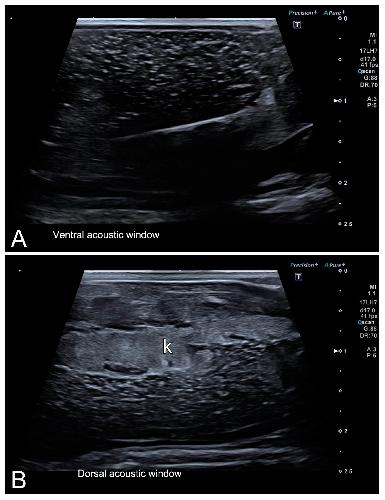

Sex Determination in Two Species of Anuran Amphibians by Magnetic Resonance Imaging and Ultrasound Techniques. , Ruiz-Fernández MJ, Jiménez S, Fernández-Valle E, García-Real MI, Castejón D, Moreno N , Ardiaca M, Montesinos A, Ariza S, González-Soriano J., Animals (Basel). November 18, 2020; 10 (11):